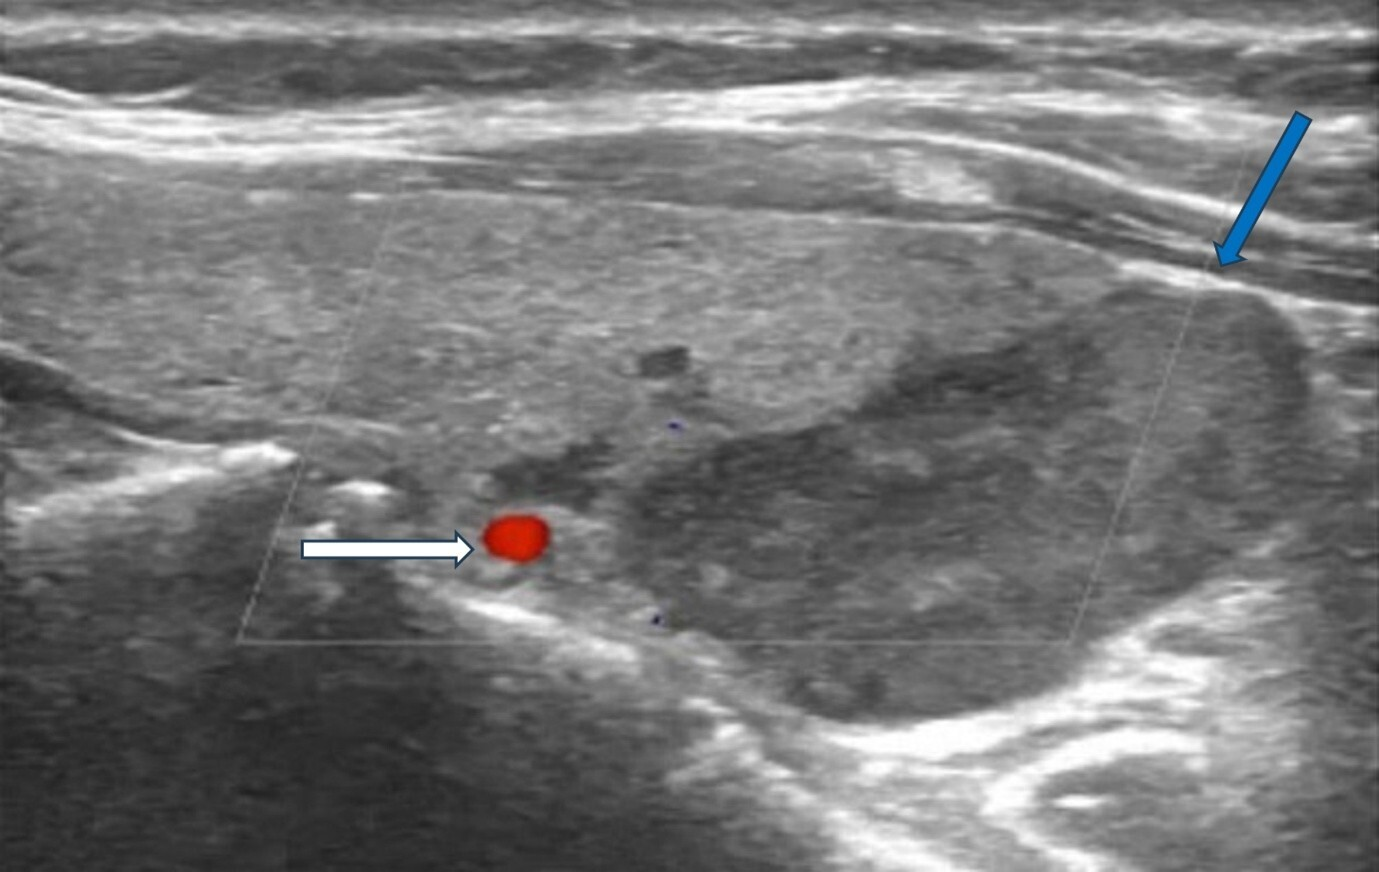

Sonographic features indicative of PC typically include lesion size greater than 3 cm, substantially larger than typical benign adenomas, which generally measure 1–2 cm. Malignant lesions often exhibit irregular or lobulated margins with evidence of invasion into adjacent tissues, in contrast to the smooth, well-circumscribed borders characteristic of benign counterparts (Figure 1).

Figure 1. Ultrasonography image of parathyroid carcinoma. Legend: 65-year-old patient with parathyroid carcinoma presented with serum PTH of 1300 pg/mL (12–88 pg/mL) and Ca:13 mg/dL (8.8–10.6 mg/dL). Ultrasonography showed a hypoechoic mass with lobulated borders (32 × 23 × 14 mm) next to the lower pole of the left thyroid lobe (blue arrow). The white arrow shows the inferior thyroid artery.